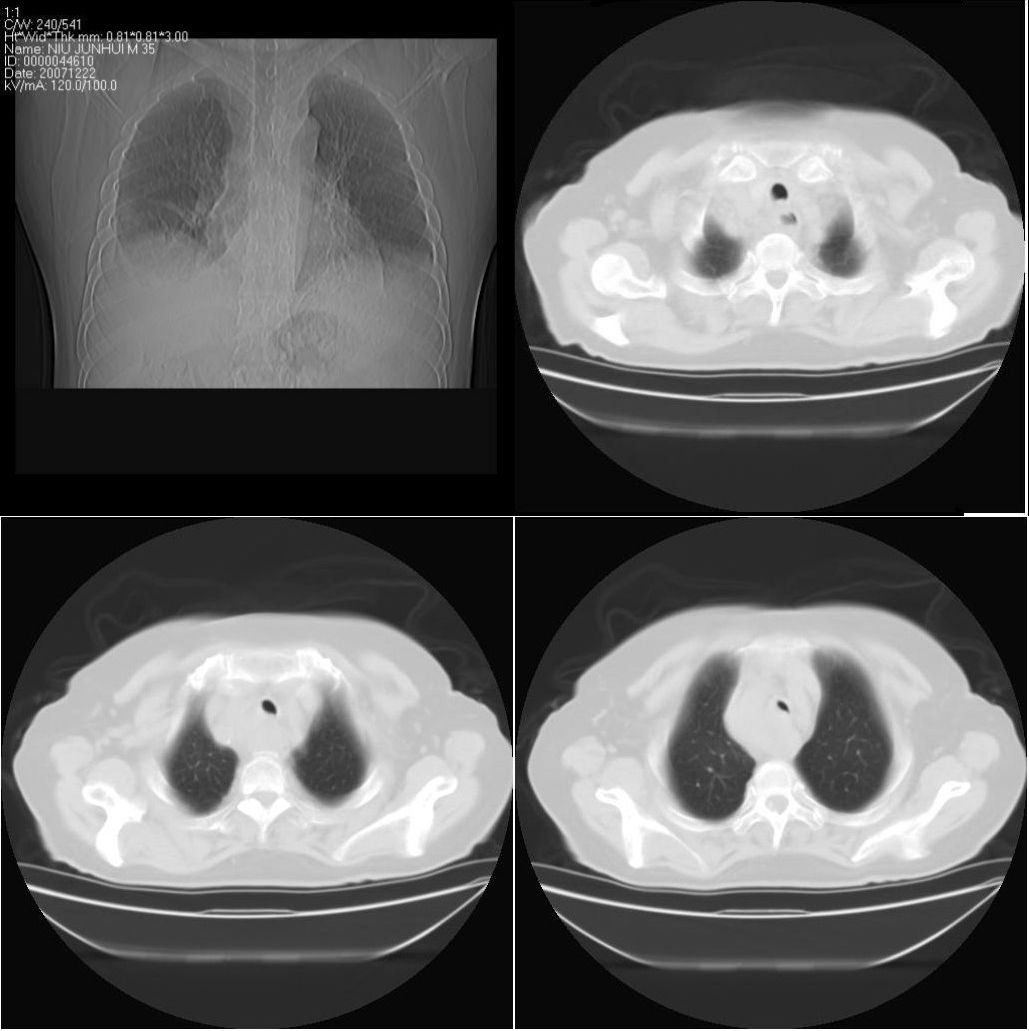

以下是引用sxlcbc在2007-12-23 4:27:00的发言:[br]气管源性肿瘤觉得有点不靠谱啊,看上去气管是受压改变的。更像是上段食管的改变,周围淋巴结肿大,食管受压。看看以下六幅图片:[br]不过,有一点不好理解:食管肿瘤应该有食道症状的,再说食管癌出现周围这么大的淋巴结也不多见啊,如果考虑淋巴瘤倒是更合理一点,这样气管,食管受压改变也许更合理一些。[br][br]